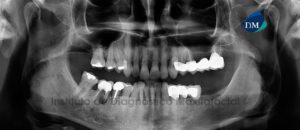

Paciente masculino, 16 años de edad, es referido al Instituto de Diagnóstico Maxilofacial (IDM) para evaluación tomográfica por retraso en la erupción de segundas premolares